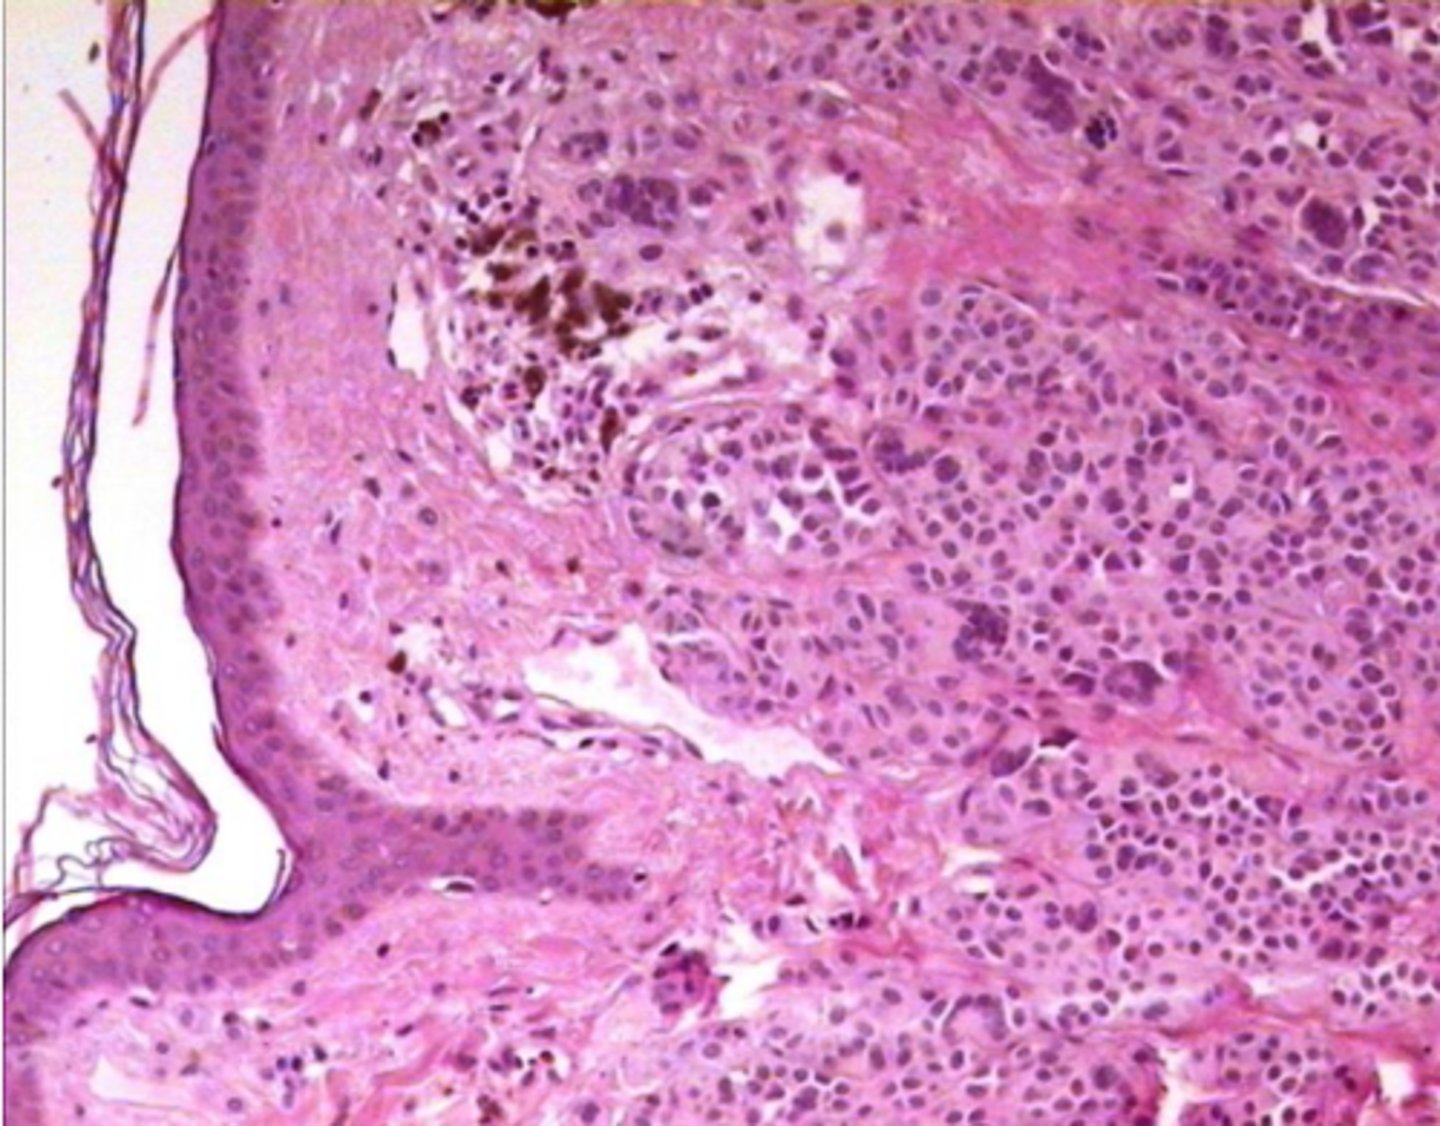

Melanoma: izteikta šūnu atipija un melanīna sintēze

Melanoma: INCI (intranukleāri citoplazmatiski ieslēgumi)